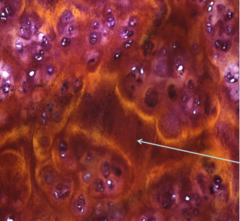

melanocyte

Front

what type of cell is this?

Back